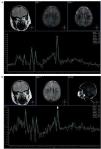

En la difusión por resonancia magnética (DWI), los túberes corticales presentan un incremento del coeficiente de difusión aparente (ADC), que expresa una expansión del espacio extracelular y se debe a la presencia de astrogliosis e hipomielinización11. A su vez, los hamartomas subependimarios pueden tener cambios en la difusión como producto de una calcificación. Generalmente se los observa isointensos en DWI y ADC, en relación con el parénquima sano (fig. 10).

Figura 10. (a) Secuencia en plano axial y ponderación T2 de un paciente de 1 año de edad que presenta hamartomas subependimarios en ambos ventrículos laterales (flechas blancas) y túberes corticales (círculo). (b) En la difusión los hamartomas subependimarios son isointensos con respecto a la sustancia blanca (flechas), mientras que en el coeficiente de difusión aparente son isointensos o levemente hipointensos con respecto a la sustancia blanca (flechas). Esto podría estar en relación con su calcificación. Los túberes corticales son hiperintensos en el coeficiente de difusión aparente (círculo), presentando difusión facilitada.

Con respecto a la espectroscopia por resonancia magnética se ha visto que en la evaluación de los túberes corticales no hay un aumento de la colina (Cho) que sugiera aumento de mitosis, pero sí se ha identificado un descenso significativo de las relaciones N-acetil aspartato/creatina (NAA/Cr) y NAA/(Cho+Cr) a expensas de un descenso del NAA (fig. 11). La reducción del NAA se debe a que las células que forman los túberes corticales producen menos NAA que las neuronas12.

Figura 11. Espectroscopia monovoxel con secuencias PRESS y tiempo de eco de 25 ms: corresponde (a) al lado normal y (b) a la evaluación de un túber cortical, donde se observa un descenso del pico del N-acetil aspartato, un incremento del pico de mioinositol y un pico normal de colina.

También se ha encontrado un incremento del mioinositol en los túberes corticales que se explicaría por la presencia de gliosis o inmadurez neuronal13.